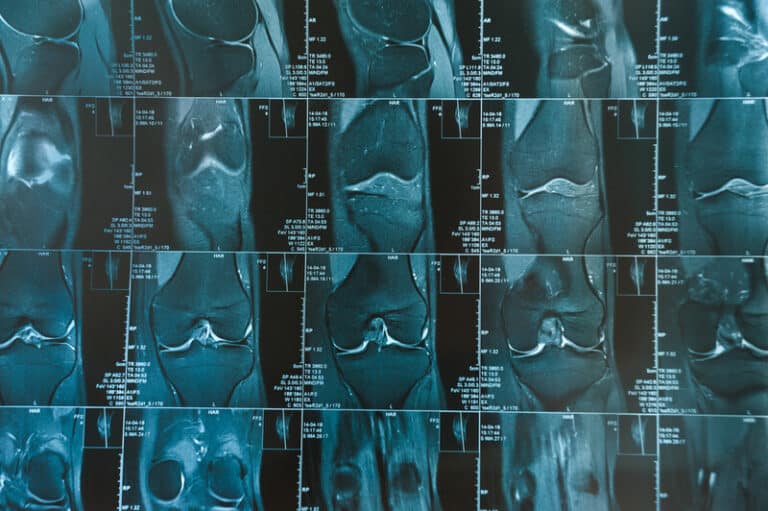

How accurate are MRI scans of the knee?

We get many emails from people who had a recent MRI. Some of their MRI reports are deep and comprehensive in their description of an unseeingly insurmountable amount of damage to the person’s knees. The person who sends in the email will sometimes add something in the email to suggest that their MRI is one … Continue reading How accurate are MRI scans of the knee?